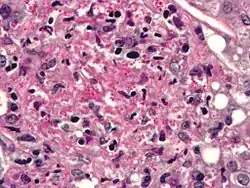

Диморфні гриби, які зазвичай зустрічаються у фекаліях птахів та кажанів.[2] Гістоплазмоз (хвороба Дарлінга — так її називають виключно тоді, коли гістоплазмоз виникає у людини) — інфекційна хвороба, яку спричиняє грибок Histoplasma capsulatum. [3]

Histoplasmosis capsulatum

Конідія Histoplasmosis capsulatum